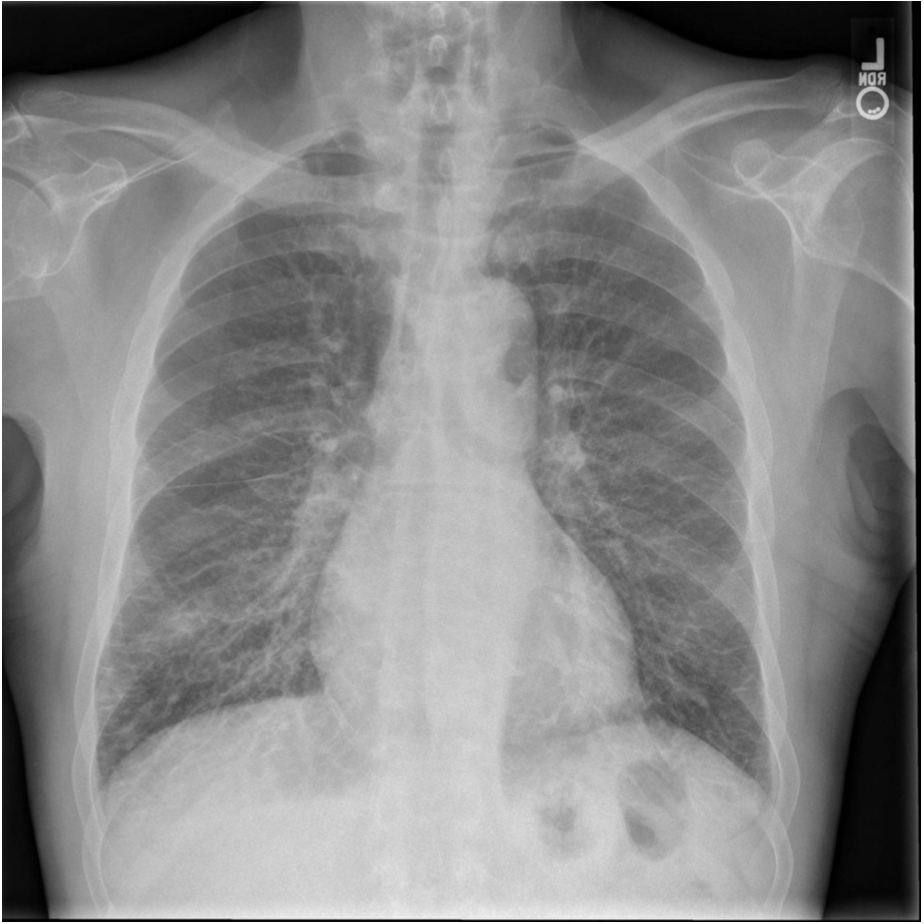

102

**Answer: Chronic Obstructive Pulmonary Disease** ## Footnote In normal subjects, the diaphragm is intersected by the 5th to 7th anterior ribs in the mid-clavicular line - in this patient you can count up to 9 ribs before reaching the diaphragm → hyperexpanded lungs. Flattening of the diaphragm is also observed in this x-ray which is a reliable feature of lung hyperexpansion.